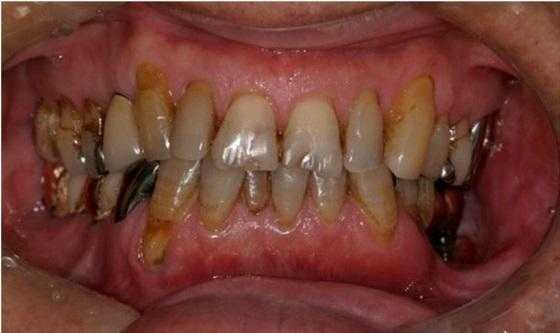

В ходе клинического исследования у пациента был обнаружен болезненный отек левой щеки и гипестезия нижней губы с левой стороны, при этом возможность открытия рта была ограничена до ширины полтора пальца, а вокруг дентальных имплантатов с левой стороны наблюдался некроз альвеолярной кости, воспаление слизистой и периодическое гноеотделение (фото 1).

Фото 1. Клиническая ситуация до лечения.